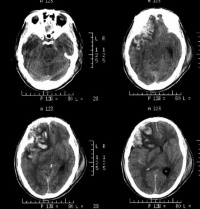

右侧颞叶脑挫裂伤

,区别只在于何者为重或何者为轻的问题。通常脑表面的挫裂伤多在暴力打击的部位和对冲的部位,尤其是后者,总是较为严重并常以额、颞前端和底部为多,这是由于脑组织在颅腔内的滑动及碰撞所引起的。脑实质内的挫裂伤,则常因脑组织的变形和剪性应力引起损伤,往往见于不同介质的结构之间,并以挫伤及点状出血为主。

对脑挫裂伤与脑震荡可以作出明确的鉴别诊断,并能清楚地显示脑挫裂伤的部位、程度和有无继发损害,如出血和水肿情况。同时,可根据脑室和脑池的大小、形态和移位的情况间接估计颅内压的高低。尤为重要的是,对一些不典型的病例,可以通过定期CT扫描,动态地观察脑水肿的演变或迟发性血肿的发生。近年来,在有此设备的医院CT已作为急性头伤的常规检查,因为单靠伤史和查体难以作出超早期诊断。Stein等(1990)指出在GCS13~15危害较小的轻型头

右额颞叶脑挫裂伤合并蛛网膜出血

伤中,首次CT的阳性发现率竟占18%,并有5%需行手术治疗,强调早期CT检查的必要性。